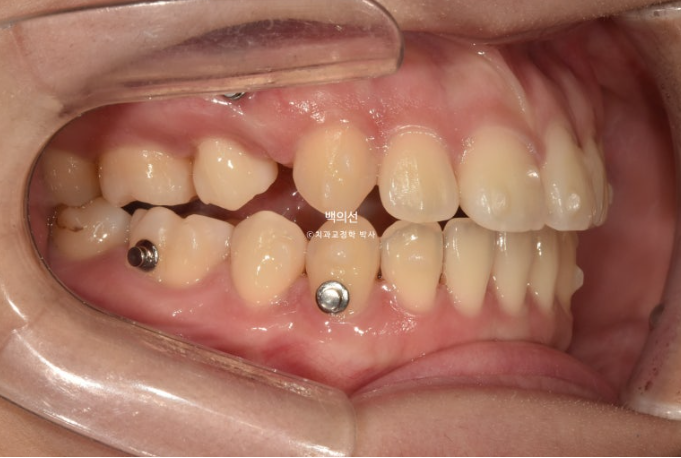

24.03

5개월에 걸친 부분교정으로 이제 겨우 어금니가 섰으니 재제작을 준비해야죠.

첫 추가장치 제작에 들어갔고 24년 4월부터 12월까지, 34개 추가장치를 모두 낀 후 모습입니다.

발치공간은 어금니 쓰러짐 없이 잘 닫혔고

양측 교합은 모두 좋습니다.

24.12

다만 앞니 중심선이 아쉽고

발치곡안이 미세하게 남아 두번째 추가장치 제작에 들어갔습니다.